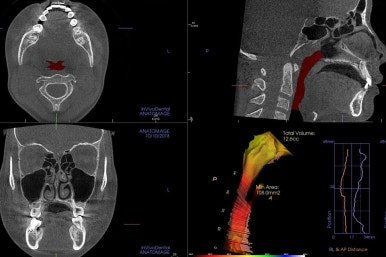

부산치아교정잘하는곳 키다리아저씨치과에 처음 오셨을 때의 X-ray 입니다.

해당 부위에 치아가 아래로 꺼져있고(가로 막혀서 나오지 못하고 있고) 주위 치아들이 기울어져 있는 것을 볼 수 있습니다.

부산치아교정잘하는곳 키다리아저씨치과에서는 첫 분석에 매우 신경을 많이 쓰는데요.

그 중 하나가 3차원 CT영상에서 이 뿌리들의 정확한 위치를 파악하고 전반적인 턱뼈의 크기 조화를 체크합니다. 필요하면 위턱뼈를 가로로 넓혀주는 악궁확장이 필요하기도 합니다.

이번 환자분은 위턱뼈가 좁은편이었고, 위턱뼈가 좁으면 콧속도 좁아서 코로 호흡하는데 문제가 있었으며 연쇄적으로 혀의 위치도 좋지 못하여 턱뼈의 성장에도 부정적인 영향을 주는 경우가 많습니다.

따라서 교정치료에 앞서 위턱은 가로로 넓혀주는 악궁확장장치(RPE)를 시행하기로 했습니다.